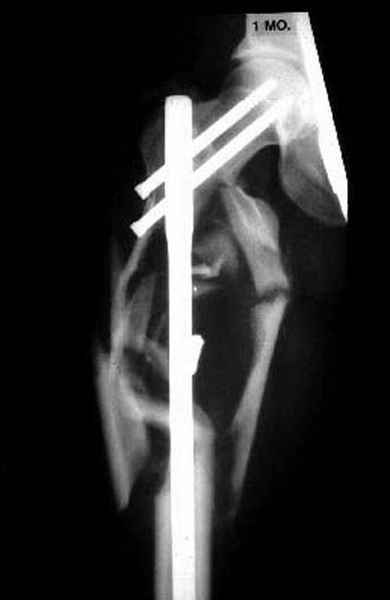

На Вашем месте мы бы сделали ретроградний интрамедуллярный штифт. Нагрузка с первых дней не самоцель, хотя 12 мм штифт с двумя интерлокинг винтами выдерживает вес 75 кг., но разработку сустава можно начать как можно быстрее.

Достаточно пары месяцев для определения нужды в дополнительной костной пластики.

2 перелом бедра